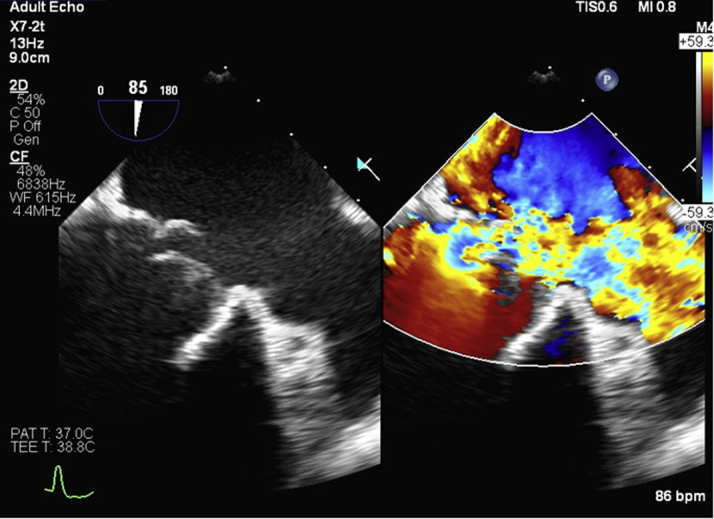

Transesophageal echocardiogram showed a flail mitral valve leaflet and severe MR (Figure 1) with a small vegetation (Figure 2). Cardiac computed tomography defined the neo– left ventricular outflow tract as having a diameter of 6 to 7 mm and an area of 2.8 cm2 (Figure 3). It also showed a hypoattenuating mass associated with the posterior leaflet, most likely a vegetation (Figure 4).

Figure 1.

Pre-Procedure Transesophageal Echocardiogram

Flail bioprosthetic mitral valve leaflet with severe mitral regurgitation.